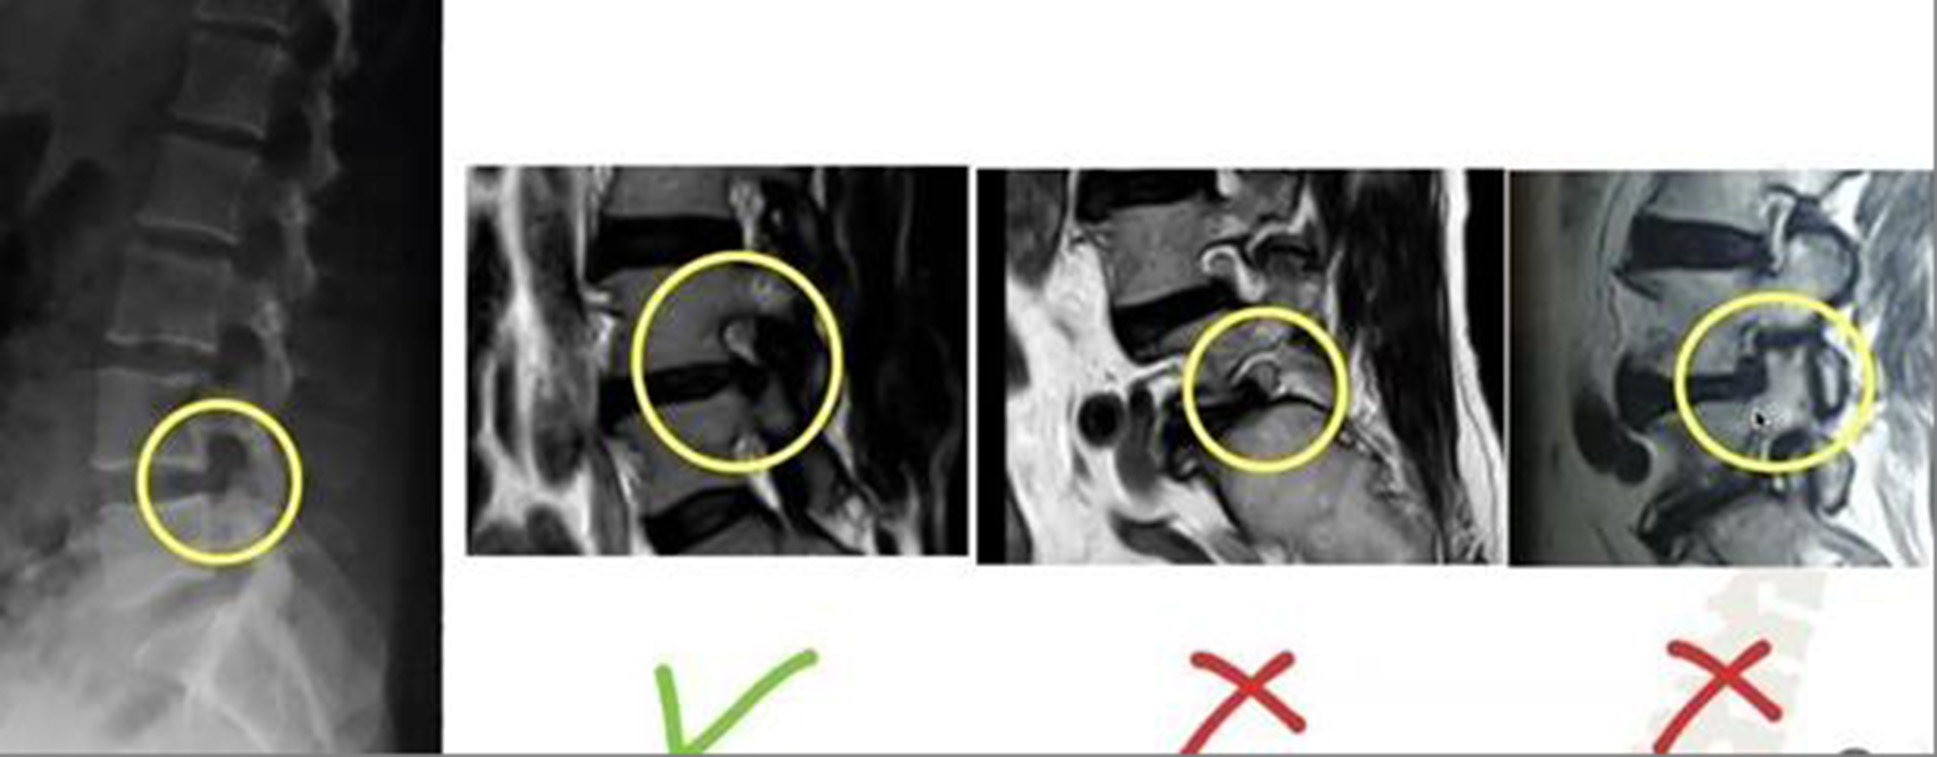

The size of the foraminal opening and the location where the nerve root exits through it (Fig. 5) [18] are of crucial importance. To enlarge the foramen and place the endoscopic port, it is necessary to preserve the anatomical structure of the foraminal opening. If the nerve root exits through its upper portion, and the lower part, even in the presence of stenosis, still has space for placing a guidewire, the intervention can be successfully performed. However, if the root exits through the lower portion of the foramen or there is significant stenosis due to spondyloarthrosis, developmental anomalies, or pronounced spondylolisthesis, the operation will be unsuccessful—except in cases of foraminal hernias, where foramen opening is not required.

Fig. 5. Possibility of intervention depending on the size of the foraminal opening and the location of the nerve root (https://doi.org/10.1002/ca.22286)